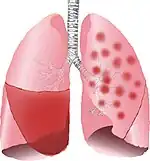

![]() | |

| Typical distribution of lobar pneumonia (left in image) and bronchopneumonia (right in image) | |

It is often contrasted with lobar pneumonia; but, in clinical practice, the types are difficult to apply, as the patterns usually overlap.[2] Bronchopneumonia (lobular) often leads to lobar pneumonia as the infection progresses. The same organism may cause one type of pneumonia in one patient, and another in a different patient.